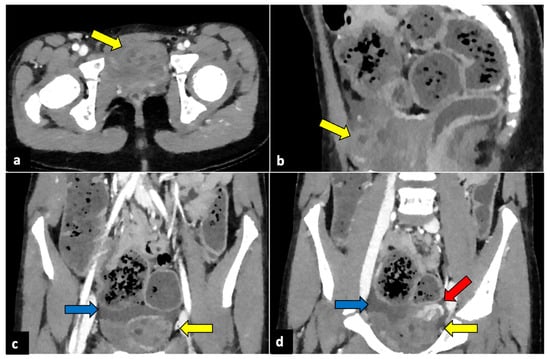

Although CT is not indicated as a first-line technique when OT is suspected, it is usually performed in female patients with aching nonspecific pelvic pain and vomiting. Moreover, it can be helpful for ruling out OT if US does not show ovarian abnormalities or if it is limited due to patient pain. CT scans usually show a large pelvic mass abnormally located at the midline, anteriorly to the uterus. During no-contrast scans, the ovary may appear hyperdense (>50 Hounsfield Unit) due to internal haemorrhage. In contrast-enhanced images, the ovarian twisted pedicle may be detected [27,28]. It can also be seen as a triangular enhancing soft tissue between the uterus and the involved ovary. Peripherally displaced follicles, fat stranding near the adnexa, and a small amount of free fluid are also common findings (Figure 2) [26].

Figure 2.

Left ovarian torsion in a 12-year-old woman with acute lower abdominal pain and vomiting. Axial (a), sagittal (b), and coronal (c,d) contrast-enhanced CT images show enlarged and oedematous left adnexa migrated to the midline and anteriorly to the uterus (yellow arrows), with peripherally displaced ovarian follicles. A small amount of free pelvic fluid (blue arrows) is associated. On the coronal plane, the twisted and oedematous ovarian vascular pedicle (red arrow) can be easily detected.